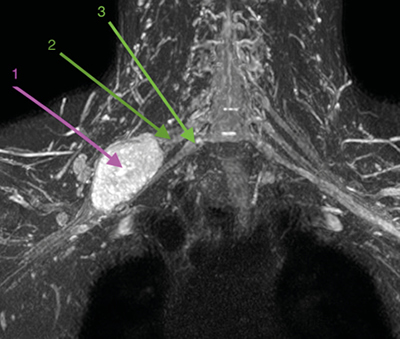

Figura 2

Presentamos el caso de un paciente diagnosticado de schwannoma de plexo braquial con efecto compresivo creciente, a quien se le plantea tratamiento con toxina botulínica en los músculos escalenos.

La toxina botulínica es una neurotoxina sintetizada por la bacteria clostridium botulinum. Su mecanismo de acción consiste en bloquear selectivamente los receptores colinérgicos de la unión neuromuscular, produciendo una parálisis neuromuscular temporal y reversible, recuperando la función en aproximadamente tres a seis meses.